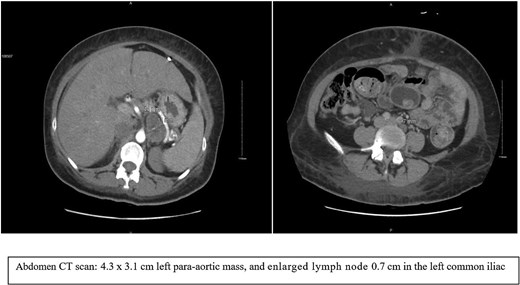

A PET/CT scan (Fig. 3) showed mild heterogeneous fluorodeoxyglucose (FDG) uptake in a mixed-density left adrenal mass with calcifications. The radiologist suspected a left adrenal mass, with differential diagnoses including pheochromocytoma or previous hemorrhage.

PET-CT scan showed heterogeneous FDG uptake in a mixed-density left adrenal mass with internal calcifications.